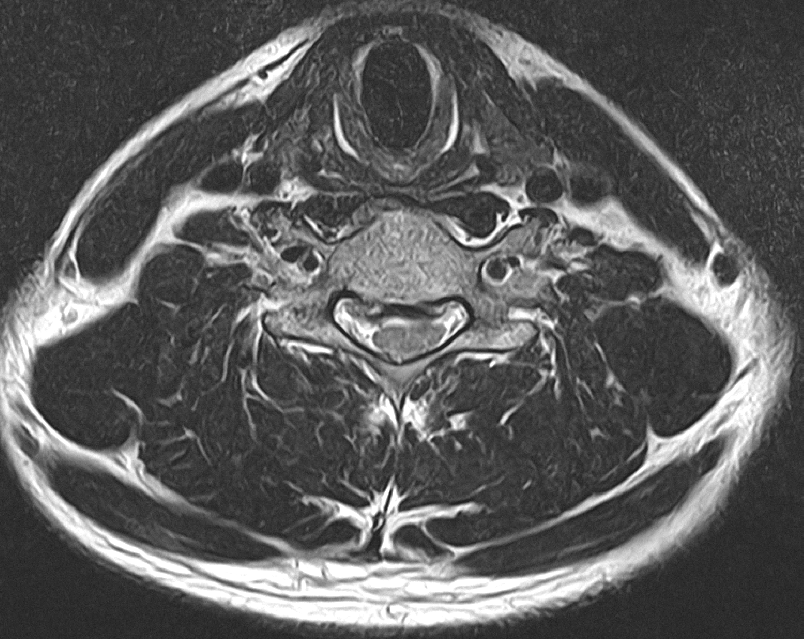

• 1번 째 사진

아마 올려주신 사진중에서 두번째 사진이 디스크가 가장 많이 튀어나온 부위의 단면일 거라고 예상됩니다.